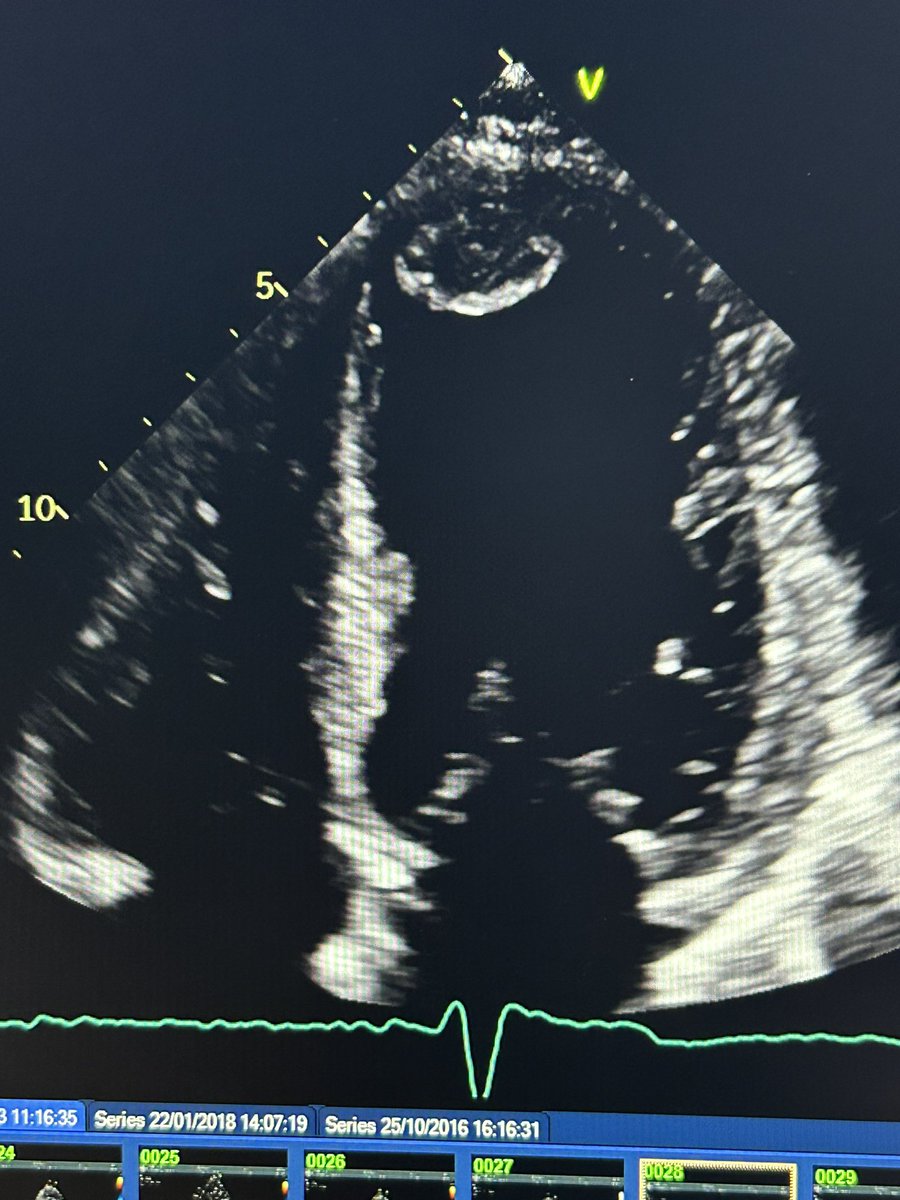

What do you think of this apical 4 chamber view? Doesn’t look terribly foreshortened. Would you both seeing if there’s anything better?

What about now you see it moving? Still confident you’re not foreshortened?

I agree there’s good endocardial definition and perhaps volumetric assessment won’t be too challenging here.